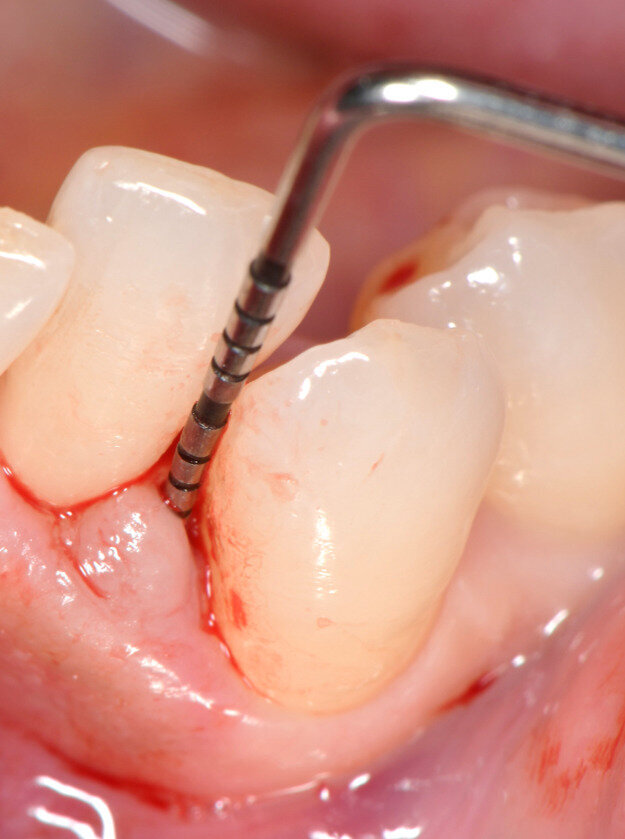

Fig. 3 - Caso clinico illustrativo. Visione frontale del difetto iniziale. I tessuti appaiono edematosi, la papilla interdentale è rigonfia e distaccata dalle superfici dei denti contigui.

Fig. 4 - Sondaggio parodontale. PPD di 6 mm e CAL di 7 mm per l’elemento 33.